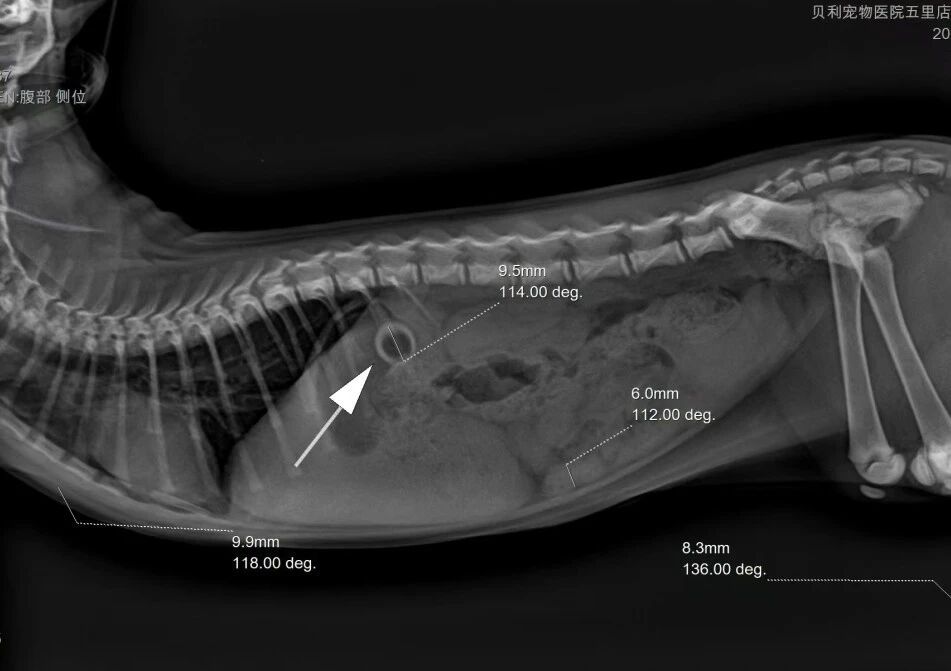

Afin d'évaluer plus précisément les risques potentiels, un examen d'imagerie a été réalisé. Les résultats ont clairement révélé une opacité importante au niveau de l'estomac. Compte tenu du témoignage du propriétaire, qui a décrit le chaton mordant et avalant la tétine du biberon, le vétérinaire a établi un diagnostic précis : un cas typique d'ingestion d'un corps étranger gastrique.

L'imagerie diagnostique a rapidement permis d'identifier le corps étranger gastrique de haute densité (la tétine du biberon), définissant clairement son emplacement et le risque potentiel, et fournissant une base fiable pour un traitement ciblé.